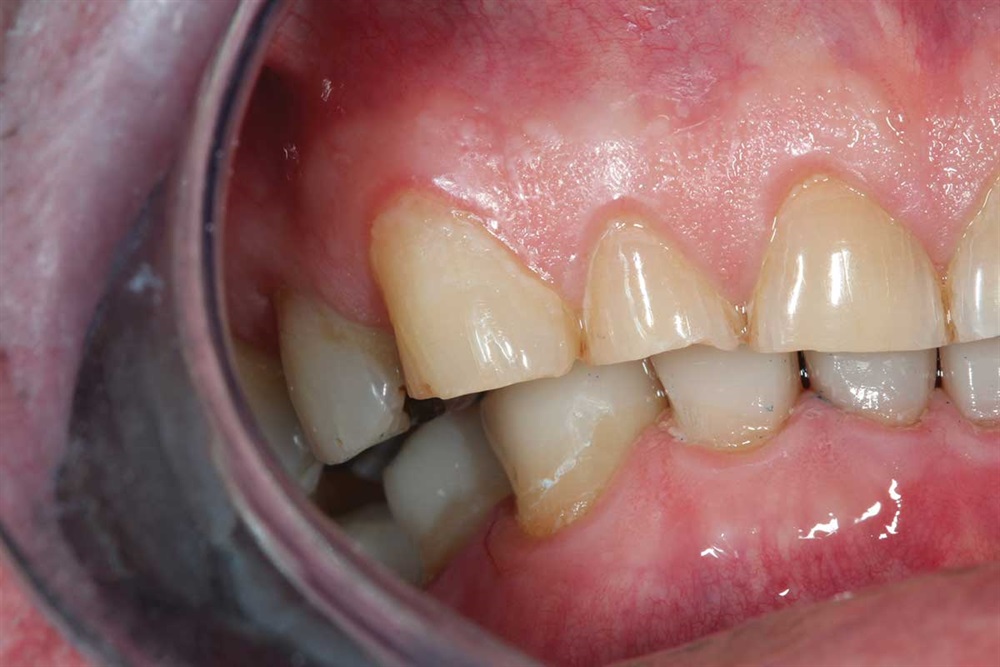

Fig. 14–16: It is hard to see, but the patient’s bicuspids nearly miss in occlusion because the upper bicuspids are buccal to his lower bicuspid. One reason for ortho would have been to expand the lower arch to get more occlusion on the bicuspids.

Fig. 15

Fig. 16